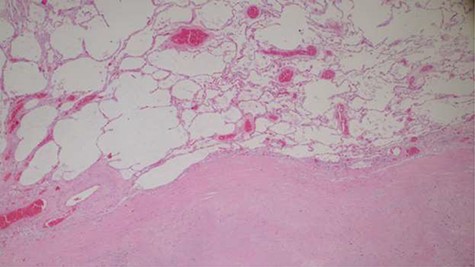

Histopathology analysis of the lung specimens revealed mixed chronic inflammatory infiltrates associated with pulmonary vascular thrombosis and areas of extensive necrosis (Figs 3 and 4). Bowel tissue sections revealed severe ischemic necrosis and mesenteric vessel thrombosis (Fig. 5). Thus, the primary causes of death were ruled to be ischemic colitis and pulmonary thrombosis due to COVID-19. The underlying disease conditions contributing to the cause of death being hypertensive heart disease, diabetes mellitus and septicemia.

Histopathology of lung tissue showing mixed chronic inflammatory infiltrates and vascular thrombosis (hematoxylin and eosin ×100).